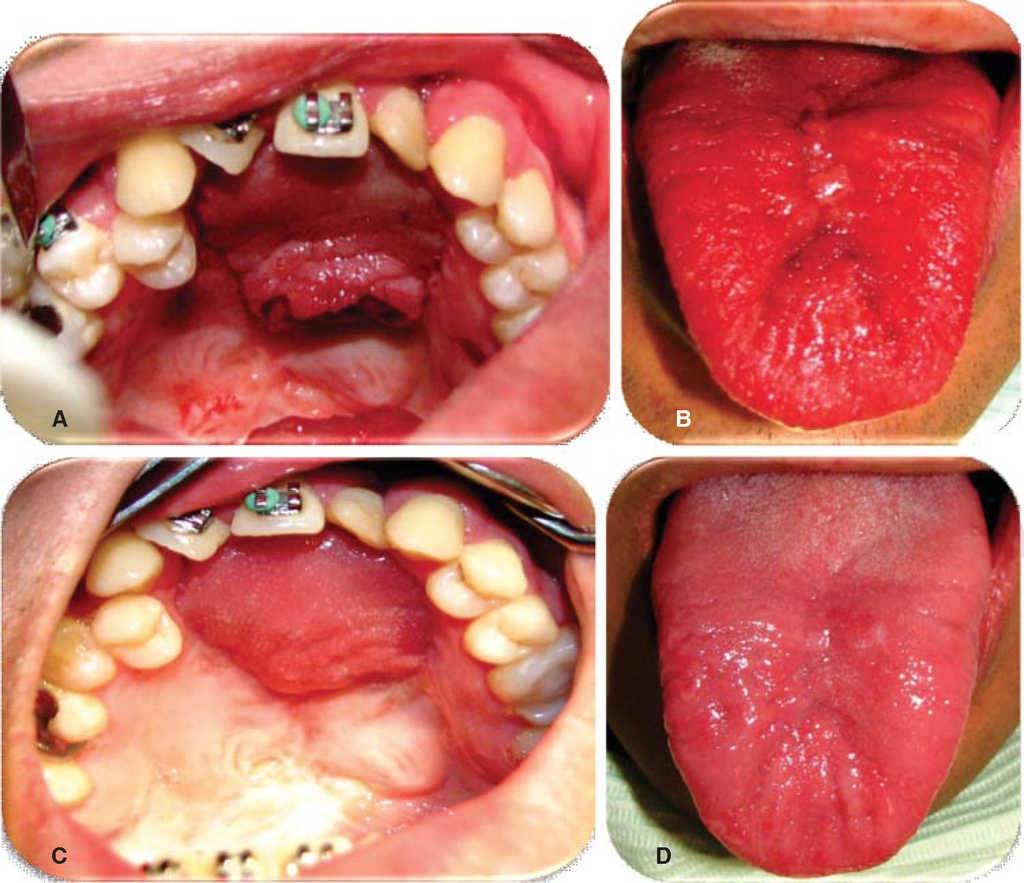

Evolution. Weekly controls were conducted at 7, 14, 21 and 28 days after surgery. At controls executed at 7, 14 and 21 days, excellent evolution was observed: with well-hydrated mucosa of suitable color, surgical wounds free of dehiscence, infection or compromised vascularity (Figures 5 and 6). Suitable tongue mobility was observed without phonation alterations. On day 21, under local anesthesia the tongue flap was separated with clamps, no accidents or complications were encountered. The patient was programmed for another visit seven days later, and was prescribed with amoxicillin, by mouth, 500 mg every eight hours and ibuprofen by mouth, every eight hours for five days. At the 28th day control, clean surgical wounds were observed without signs of dehiscence or infection, as well as 100% closed oro-nasal fistula, dorsum of the tongue without functional or esthetic alterations. The patient was discharged and programmed for a one month later control appointment.

Figure 6 Tongue flap clamping and removal. A. Surgical bed; removal of tongue flap. B. Surgical bed: donor site. C. 100% closure of palatal fistula. D. Donor site suture.